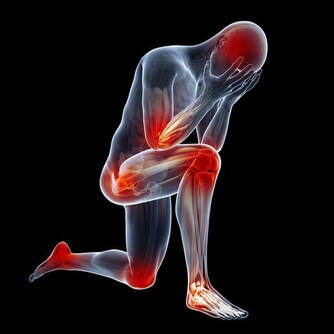

心絞痛的發作有兩種形式,一種是典型發作,這種非常好鑑別,發作的位置是在心前區,並且有壓榨憋悶的感覺,在舌下含服硝酸甘油之後,就能夠得到明顯的緩解,這就是很典型的心絞痛。但是心絞痛有很多時候發作起來並不典型,有的時候,發作的部位是在胃脘部,有的時候僅僅是左側肩臂疼痛,這些疼痛只是一過性的,這就很難鑑別。

一般心臟導致的疼痛呈壓榨性的,憋悶的疼痛。一般舌下含服硝酸甘油之後,可以在一到兩分鐘內消失,很少有疼痛超過五分鐘的,所以有這些典型的表現,還是不難鑑別胃痛與心絞痛的。